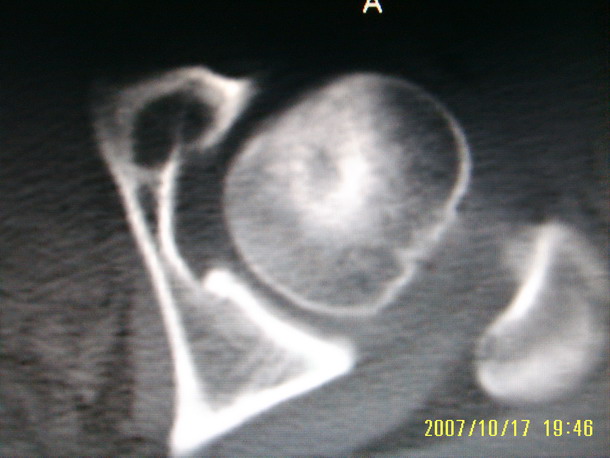

标题: CT10352:女,45岁,股骨头病变,如何诊断? [打印本页]

标题: CT10352:女,45岁,股骨头病变,如何诊断?

股骨头病变,如何诊断?

患者女,45岁,左髋部行走疼痛一年,无外伤史,无感染史。x片示囊状骨透亮区

左侧股骨头变形,密度增高,局部塌陷。多考虑:股骨头缺血性坏死伴退变!

左侧股骨头塌陷,其内囊变硬化,骨纹理改变考虑:左侧股骨头坏死及蜕变.

股骨头形态尚可,骨皮质环厚度及完整性可,病灶区以外骨质尚未见明显异常,临近髋臼骨质亦可见类似改变,考虑退变性关节面下囊变可能性大,骨样骨瘤等不排除,

股骨头形态尚可,骨皮质环厚度及完整性可,病灶区以外骨质尚未见明显异常,临近髋臼骨质亦可见类似改变,考虑1.动脉瘤样骨囊肿,2.股骨头缺血坏死,

股骨头形态尚可,骨皮质环厚度及完整性可,病灶区以外骨质尚未见明显异常,临近髋臼骨质亦可见类似改变,考虑退变性关节面下囊变可能性大

双侧股骨头形态都欠规整,外形欠光滑,尤以左侧明显,考虑双侧髋臼发育不良并退行性变